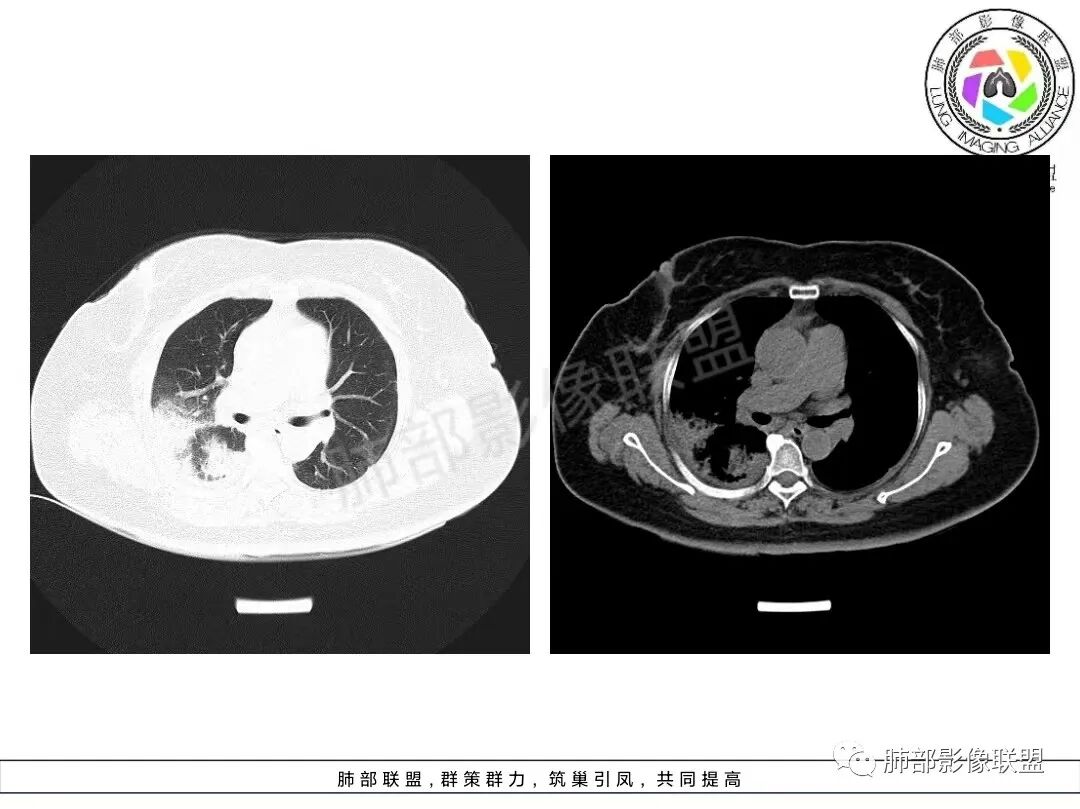

两肺沿胸膜下分布为主,大片、斑片状不均质实变,肺窗>纵隔窗,提示累及肺实质和间质,实变内充气支气管征空洞几乎不见,边缘收缩凹陷,部分平直,肺体积整体未见缩小。临床血氧降低,白细胞升高,考虑OP,COP,鉴别隐球菌,粘液腺癌!

老年女性,咳嗽、咳黄白痰,无发热,化验炎性指标高,右肺胸膜下实变,其内支气管充气、扩张,周围索条,左肺胸膜下多发结节及斑片实变,胸膜下线影,右侧少量胸水,考虑机化性肺炎,鉴别隐球菌、粘液腺癌

双肺胸膜下多发斑片及大片实变影,边缘清晰,长轴平行于胸膜,部分病灶呈细网格状,右侧胸膜增厚,右侧叶间胸膜增厚,血糖高,感染指标高,考虑OP,鉴别隐球菌

老年女性,呼吸道亚急性病程,低氧血症,糖尿病,皮炎。化验:CRP明显升高,PCT不高,蛋白低,血管炎阴性。胸部CT:双肺胸膜下分布实变和磨玻璃影,考虑间质性病变,皮肌炎可能。

2、影像特点:双肺胸膜下为主、多发斑片影、结节样实变影及磨玻璃样密度影,大部分病灶边缘平直、边界清,磨玻璃密度病灶内可见细网格影,部分病灶内可见支气管扩张表现,部分支气管直达远端,部分中断于病灶中部。部分病灶有侧向融合趋势。

影像上双肺多发磨玻璃影及实行密度影,对称分布趋势,op样改变,结缔组织相关性疾病需要排除。临床上可进一步查皮肌炎相关指标、仔细进行体格检查看看患者皮肤等情况。